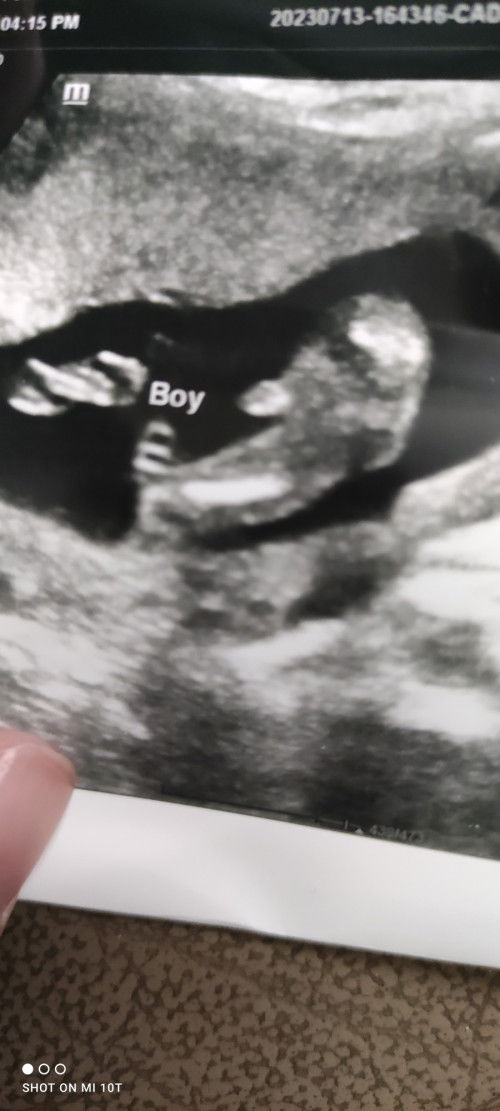

Hi,harini sy dtg klinik swasta saja2 check perkembangan baby..tp doc tolong cuba tengok gender terus..kebetulan da nampak gender,jelas nampak pistolnya😂 😍😍baby boy mmng senang nmpk gender kot...🥰..tapi sy was2 jugak,Sbb baby keluar baru Kita sure 100%..Ada tak yg scan baby boy,tapi keluar girl?😂 #gender #BabyBoy